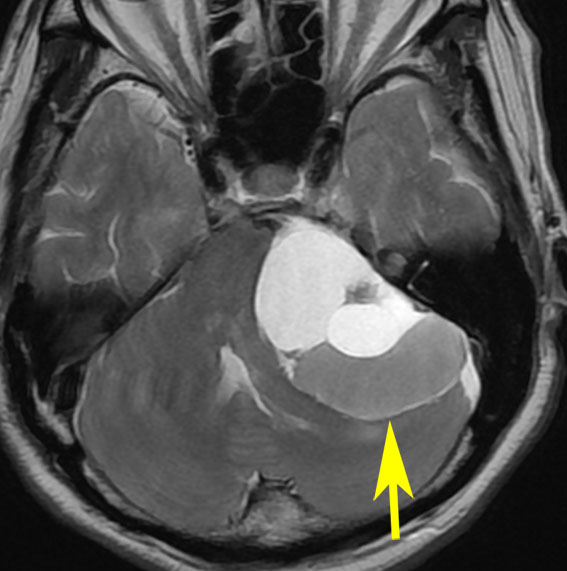

腫瘍が嚢胞性拡大で大きくなって,腫瘍内出血して,閉塞性水頭症になって意識障害を生じた患者さんです。このような事態になると臨時手術で腫瘍を摘出します。

大きなのう胞性聴神経腫瘍です。いくつかの袋が重なって腫瘍を形成しています。橋や延髄(脳幹部)が変形して,第4脳室がつぶれて閉塞しています。袋の周りが白く線状に造影されているのですが,この袋の壁だけに腫瘍細胞がありますから,これを剥がすように摘出します。顔面神経が薄くなって袋の壁にくっついているのですが,袋を破ってくしゃくしゃにすると顔面神経の位置が変わってしまって,顔面神経を損傷することがあるので要注意です。のう胞性聴神経腫瘍の方が顔面神経麻痺の後遺症の頻度が高いという報告もあるくらいです。この患者さんは迷走神経と舌咽神経の圧迫も強くて,ご飯を飲み込むことが難しくなっていました(嚥下障害)。

また,この患者さんは急に容態が悪くなって意識障害となりました。何故なら腫瘍の内部で出血したからです(黄色の矢印の部分)。第4脳室が詰まって閉塞性水頭症になって側脳室が拡大しています(右の画像)。